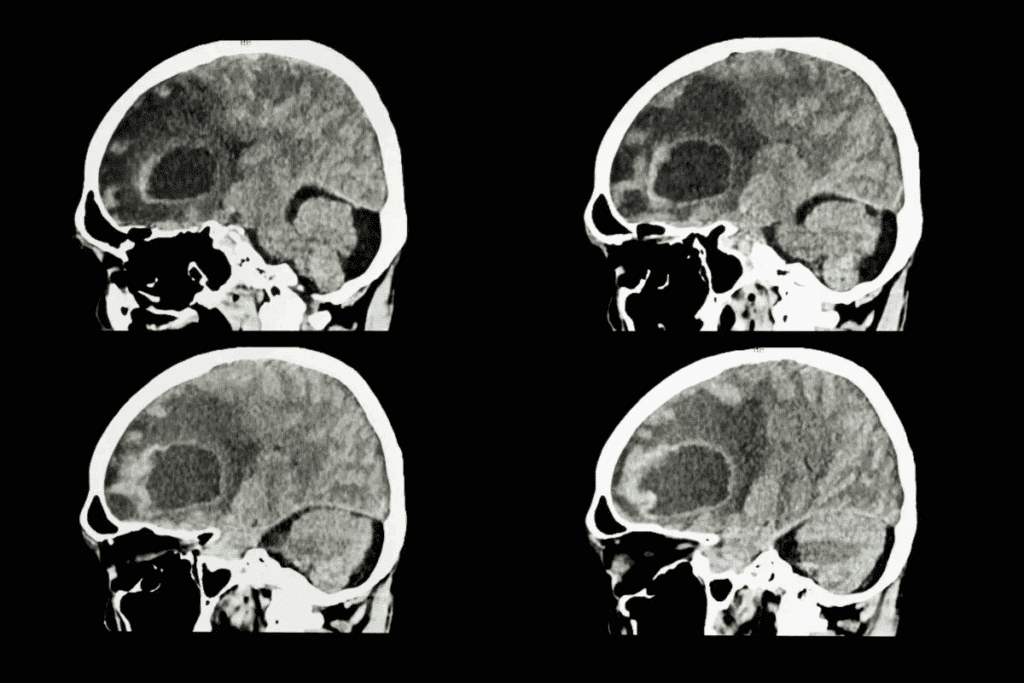

Diagnostic Imaging Techniques

Imaging is a big part of finding skull base tumors. MRI (Magnetic Resonance Imaging) and CT (Computed Tomography) scans are key tools. MRI shows soft tissues well, while CT scans focus on bones. These help doctors see the tumor’s size, where it is, and how it affects nearby areas.

Imaging techniques help find the exact location and size of the tumor. Knowing this is important for planning the surgery. MRI and CT scans give detailed info on the tumor’s size and where it is in relation to other parts.

Pre-Surgical Imaging and Planning

Imaging tests like MRI and CT scans are very important before surgery. They give the surgical team clear pictures of the tumor and the area around it. This helps them plan the best way to do the surgery.